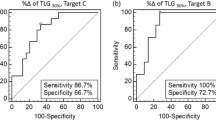

The Kaplan-Meier estimates for the median PFS were almost identical for patients with and without a morphological response: 10.9 and 10.8 months, respectively (p = 0.93). The median OS in patients with a morphological response was 51 months and in nonresponders was 39 months, but this difference was not statistically significant (p = 0.24). The survival curves are shown in Fig. 2.

The median PFS and OS were similar in patients with SUVmax above and below the median of 5.2: 11.4 vs. 10.4 months (p = 0.81) and 47 vs. 48 months (p = 0.88), respectively. In contrast, a low follow-up SUVmax had a beneficial effect on both PFS and OS. Patients with a follow-up SUVmax higher than 2.85 had a median PFS of 10.4 months compared with 14.7 months in those with a low follow-up SUVmax. Patients with a high follow-up SUVmax had a median OS of 32 months, whereas the median OS had not been reached in those with a low follow-up SUVmax. This survival benefit was significant for both PFS (p = 0.01) and OS (p = 0.003). Survival curves stratified by follow-up SUVmax are shown in Fig. 3. On the other hand, the difference between baseline and follow-up SUVmax values (∆SUVmax) appeared to have no prognostic value. The median PFS and OS in patients with ∆SUVmax above and below the median of 26.9 % were 10.2 vs. 10.9 months (p = 0.39) and 47 vs. 51 months (p = 0.51), respectively. Recently, Heijmen et al. found a coefficient of repeatability of SUVmax of 33.3 % in untreated liver metastases [28]. Using this value as a cut-off, similar results were found: the median PFS and OS in patients with ∆SUVmax above and below 33.3 % were 11.4 vs. 10.9 months (p = 0.73) and 48 vs. 51 months (p = 0.47), respectively.

The baseline SAM was not significantly correlated with PFS (p = 0.38) or OS (p = 0.88), as the median PFS and OS estimates were almost identical between those with a baseline SAM above and below 65 (11.4 vs. 10.4 months for PFS and 47 vs. 48 months for OS, respectively). In contrast, both follow-up SAM and ∆SAM values appeared to be significantly correlated with PFS and OS. When dichotomized according to their median values, the patients were categorized into identical groups. The group with a high follow-up SAM and a low ∆SAM had a median PFS of 9.4 months, and the other group had a median PFS of 14.7 months (p = 0.002). The median OS in the former group was 32 months, whereas the median OS had not been reached in the latter group (p = 0.002). The corresponding survival curves are shown in Fig. 4.